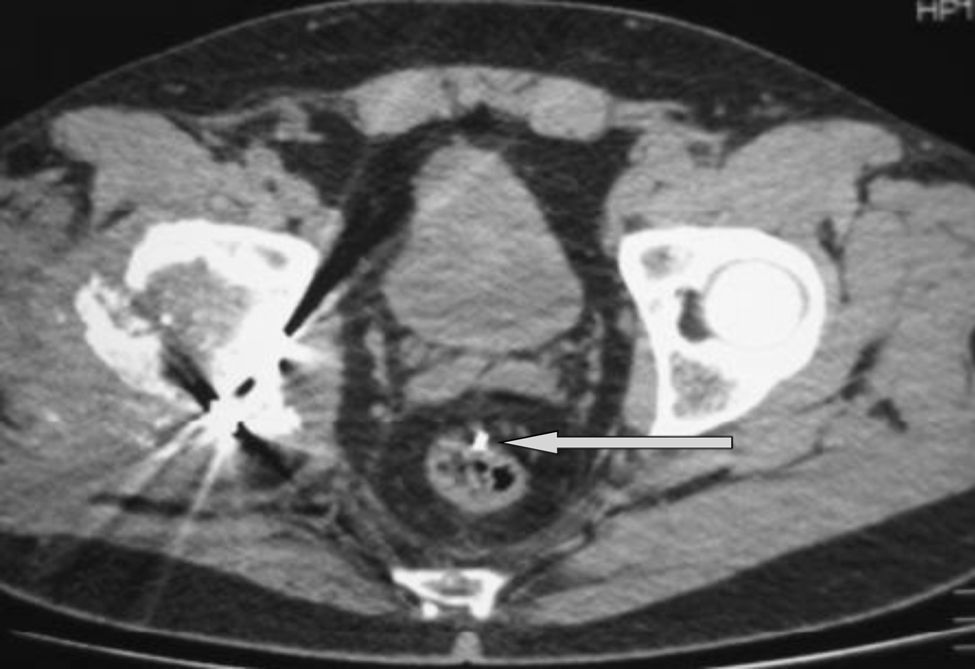

Se realiza una radiografía de abdomen y posteriormente una TC, diagnosticando la migración intraperitoneal a pelvis izquierda contralateral de la AK (fig. 1), en contacto con la pared del recto-sigma sin existir perforación (fig. 2).